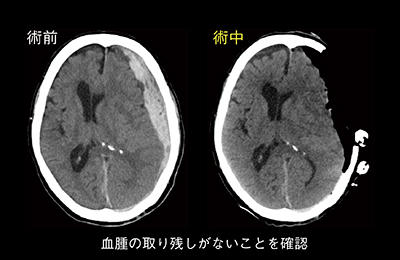

Artis zeegoの術中コーンビームCT(syngo DynaCT)は有益なデータを提供するが,密度分解能が格段に高いCTの臨床でのメリットは大きい。脳神経外科では,急性硬膜下血腫の手術の際に,開頭したままCT撮影を行い,血腫の取り残しなどを確認して進めている(図4)。呼吸器外科では,“全身麻酔下肺腫瘍マーキング”(図5,6)を行っている。通常であればCT室で局所麻酔による穿刺,胸腔鏡下手術(VATS)用のVATSマーカーの留置や色素によるマーキングを行い,その後手術室に移動して全身麻酔となる。当院では全身麻酔後にCT透視下マーキングが可能で,患者への負担も軽減できる。また,肝臓外科の直腸がん肝転移巣の切除では,化学療法が著効し,エコーなどの画像上で確認できなくなった腫瘍を切除する際に,開腹して肝臓の腫瘍があると思われる部分に直接針を穿刺し,その状態で術中CTを撮影。針の位置を目安として肝腫瘍の切除術を行っている。

図4 脳神経外科における急性硬膜下血腫の術中CT画像